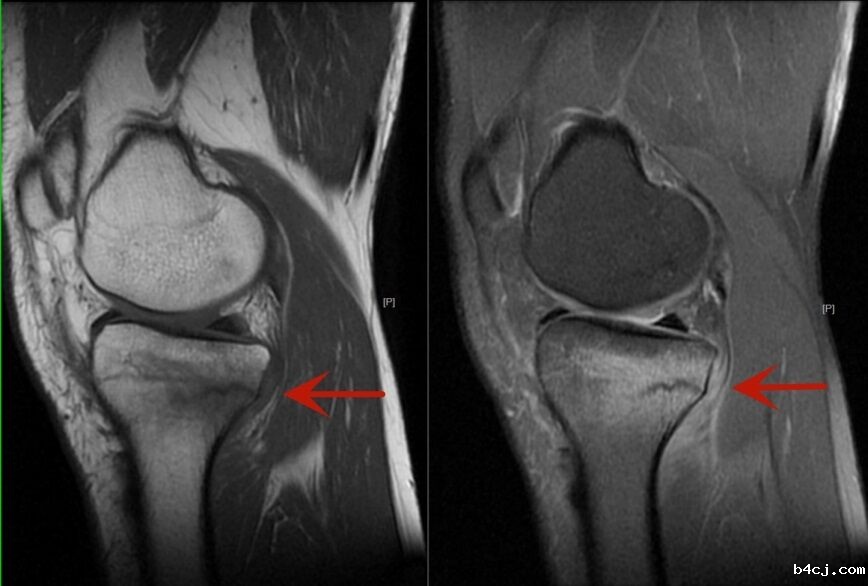

走路也会骨折么?会的。近日,40岁的张先生,自觉双膝疼痛半个月,起初并没在意,可随着日常走路疼痛逐渐加重,于是前来我院放射科拍了X光片(图1),但是并未发现异常,于是又听从医生的建议进行了膝关节的磁共振检查(图2)。最后的诊断结果为应力性骨折。

图2

放射科主任王艳玲表示,一旦有类似活动后疼痛的症状,需要及时来医院就诊,而不是强撑继续活动,以免耽误治疗。建议首诊X线摄片,X线摄片是基础检查,空间分辨率高;除了排查骨折,还要发现骨折以外的病变,对于骨关节磁共振检查不可或缺,磁共振可以发现骨髓水肿,骨挫伤。